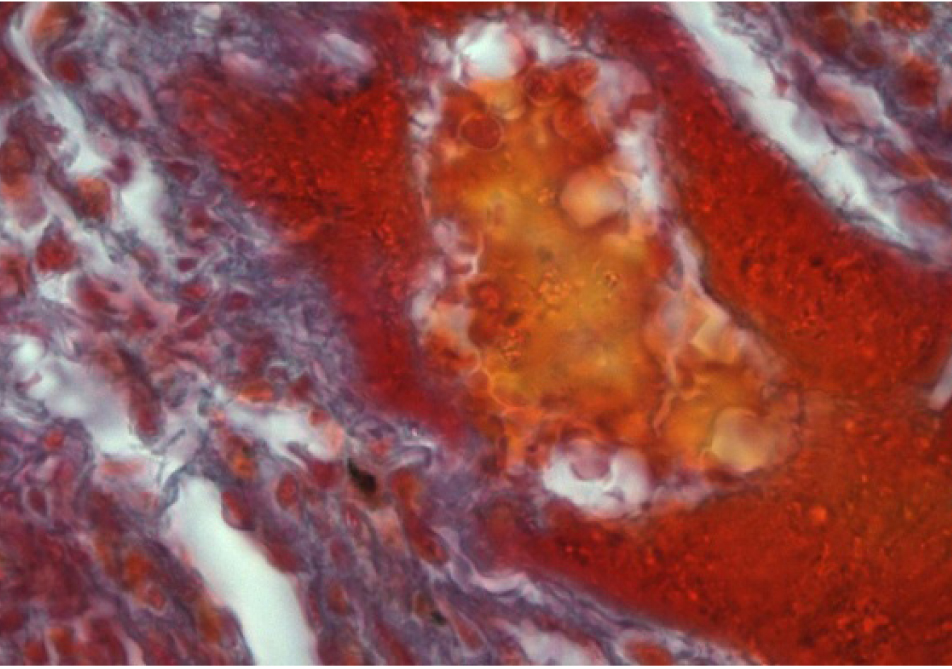

Наблюдается активизация фибробластов, окруженных пучками коллагеновых волокон (рис. 3, 4).

Рис. 3. Образование коллагеновых волокон в интерстици- альной ткани легкого. Окраска по Маллори. Ок. 10. Об. 100. Иммерсия

Рис. 4. Образование коллагеновых волокон в стенке сосуда. Окраска по Массону. Ок. 10. Об. 100. Иммерсия